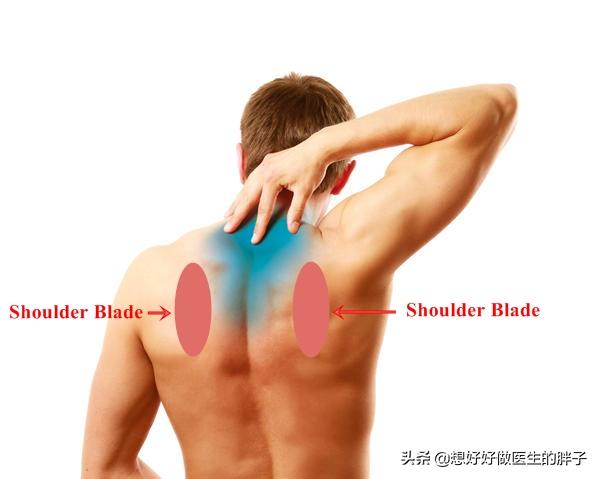

Pour les douleurs dans ce domaine, il est important de déterminer d'abord la nature de la douleur.La localisation exacte de la douleurAujourd'hui, le Dr Kong va vous en parler. Douleur dans la région de l'omoplate, comme le montre la photo suivante :

Dans la figure.L'inconfort dans et autour de la zone encerclée en rouge est appelé douleur dans la région scapulaire.. Il est donc possible de se demander s'il est possible que vous ressentiez souvent des douleurs à l'un de ces endroits, quelque part, quelque part ? La cause relative de la douleurIl y a de nombreuses raisons à cela, comme une hernie discale cervicale ou une posture corporelle anormale.Ensuite, examinons spécifiquement les zones et les causes qui provoquent généralement des douleurs.

J'ai écrit à de nombreuses reprises sur les douleurs d'épaule et de dos, mais c'est la première fois que j'écris sur la douleur dans la région de l'omoplate, dans la zone de l'image ci-dessous. En général, il peut s'agir d'une tension sur le groupe musculaire concerné ou de signes causés par le piégeage d'un nerf irradiant à partir du nerf, le premier cas étant principalement .......